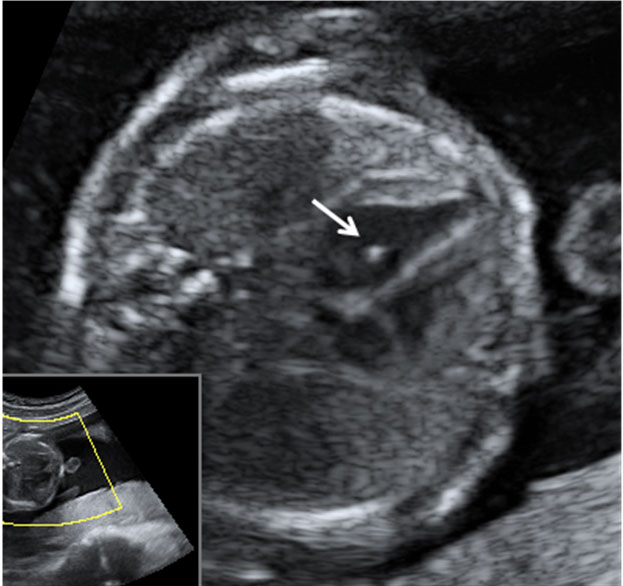

Ecografía de los dedos en la semana 12

Detalle de los dedos de una mano de un feto de 12 semanas Este bebé de 12 semanas de gestación, pone su mano en el campo de visión del ecógrafo. Por eso el especialista, comenta que "en condiciones favorables, como en este caso, pueden individualizarse los dedos". Efectivamente, podemos...